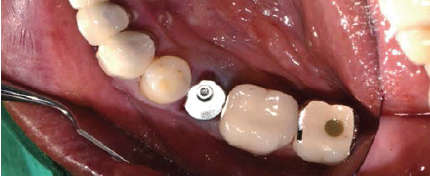

Volume Up Healing Abutment 체결

술후